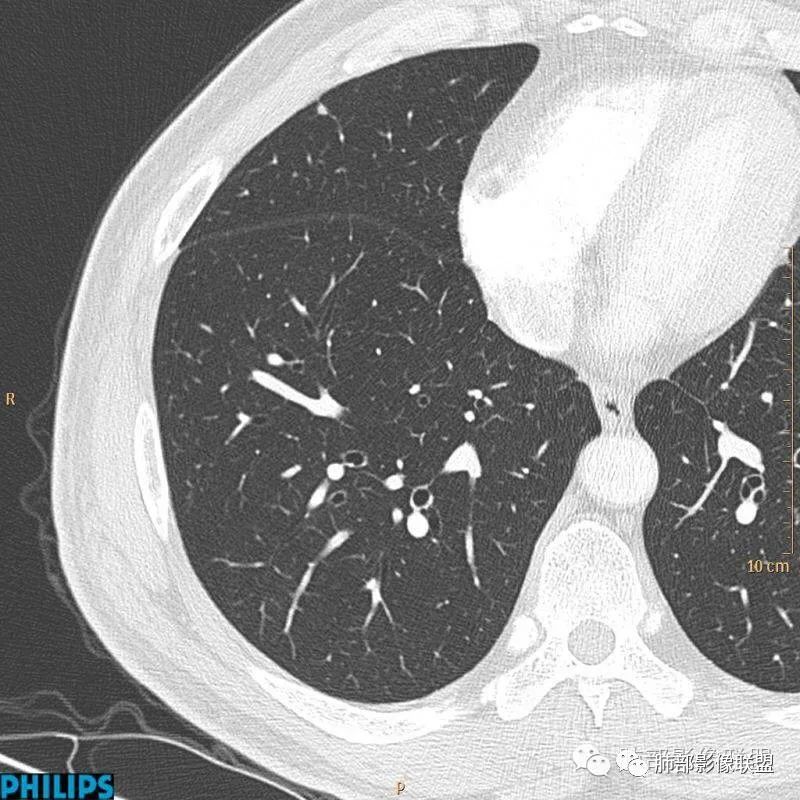

病例三:

以上病例,有什么共同点?1、病灶均位于胸膜下或叶间胸膜下;

2、病灶边缘多平直,大部分呈三角形,部分呈椭圆形;

3、病灶边缘见一条或数条细线与胸膜相连。

正常情况下,肺内淋巴结是不显示的,一般是慢性炎症所致,老年人和吸烟者多见。影像上常见于胸膜或叶间胸膜下,迄今为止,所有的报道均距胸膜或叶间胸膜小于2.0cm以内。也可以表现为与胸膜或叶间胸膜相贴的结节。绝大多数位于中下叶(气管隆突水平以下),上叶也可见到,但较少见。

长径均小于12mm。典型的形状为三角形,也可以为梭形、圆形或椭圆形。诊断的关键在于见到1-5条细线与胸膜、叶间胸膜或静脉相连,有时状如坐落于电路板的“二极管”,但以薄层CT显示为佳。有作者病理对照线状影为小叶间隔,有作者病理对照为淋巴管。其实不矛盾,因为淋巴管走行于小叶间隔内。

需要与小肺癌、肺转移瘤进行鉴别。肺内淋巴结除细线状影外,边缘清晰无分叶,无毛刺,没有磨玻璃晕,少张力等是与肺癌鉴别的关键。有作者对9例胸膜下的小于1cm的肺转移瘤进行对照,后者均为较为游离的类圆形,无线状影与胸膜或肺静脉相连。